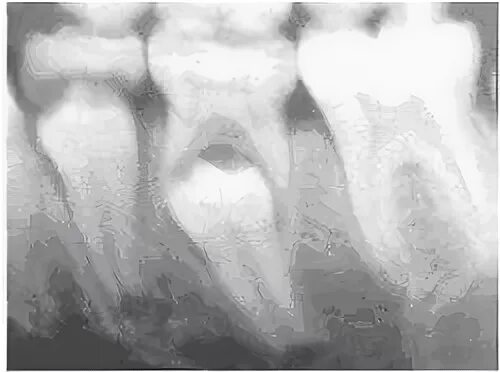

Признаки резорбции